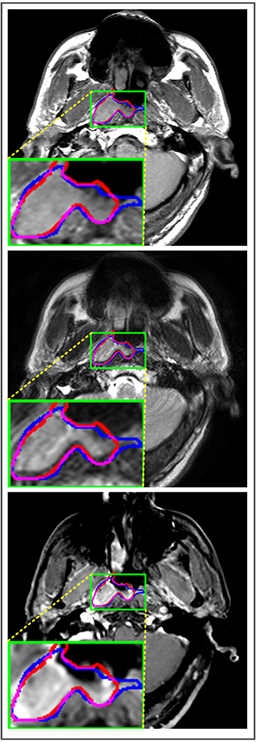

Refer to caption

(a) DSC=0.860

(b) DSC=0.853

(c) DSC=0.821

(d) DSC=0.847

Figure 8: Examples of 3D predicted results for MMFNet. The first row are ground truth, and the second row are masks predicted by MMFNet.

Figure 10: Examples of 3D predicted results for different methods. (a) Ground truth. (b) Patch-based CNN (CET1). (c) Multi-modality patch-based CNN. (d) U-net (CET1). (e) 3D U-net (CET1). (f) Input-level fusion. (g) Merging encoders’ features. (h) MMFNet + multi-MLP + stdPool + self-transfer.

Comparison with ground truth. Some predicted results of MMFNet are shown in 2D images and 3D images in Figure 7 and Figure 8. As shown in these figures, although the shape and size of NPC are varied from each other, MMFNet can still accurately determine the regions of NPC and obtain the accurate contours of tumors. Through analyzing 2D images in figure 7, MMFNet has a capacity to fuse multi-modality MRI to reduce the confusion brought by intensity’ similarity between nearby tissues and NPC. The values of meanDSC𝑚𝑒𝑎𝑛𝐷𝑆𝐶meanDSC, meanASD𝑚𝑒𝑎𝑛𝐴𝑆𝐷meanASD and meanHD𝑚𝑒𝑎𝑛𝐻𝐷meanHD of MMFNet are shown in Table 1. MMFNet can reach the best results with DSC=72.38%,meanASD=2.07mmformulae-sequence𝐷𝑆𝐶percent72.38𝑚𝑒𝑎𝑛𝐴𝑆𝐷2.07𝑚𝑚DSC=72.38\%,meanASD=2.07mm, and meanHD=18.31mm𝑚𝑒𝑎𝑛𝐻𝐷18.31𝑚𝑚meanHD=18.31mm.

Comparison with related works. Table 1 reports the values of meanDSC𝑚𝑒𝑎𝑛𝐷𝑆𝐶meanDSC, meanASD𝑚𝑒𝑎𝑛𝐴𝑆𝐷meanASD and meanHD𝑚𝑒𝑎𝑛𝐻𝐷meanHD for different methods. Predicted masks of different methods are illustrated in Figure 9 and Figure 10, which respectively present results in 2D and 3D images. Through comprehensively analyzing these results, the proposed MMFNet actually have the following properties:

(i) It directly fuses 3D MRI images rather than 2D slices. Thus, it can effectively use meaningful information from neighboring slices of MRI to realize NPC segmentation. As shown in Table 2, MMFNet can bring 12.26%percent12.2612.26\%, 8.52mm8.52𝑚𝑚8.52mm and 81.19mm81.19𝑚𝑚81.19mm improvements in meanDSC,meanASD𝑚𝑒𝑎𝑛𝐷𝑆𝐶𝑚𝑒𝑎𝑛𝐴𝑆𝐷meanDSC,meanASD and meanHD𝑚𝑒𝑎𝑛𝐻𝐷meanHD compared to the best method based on 2D images (Multi-modality patch-based CNN). And Figure 10 shows that 3D-based methods have less isolated regions (false positives) than 2D-based ones.